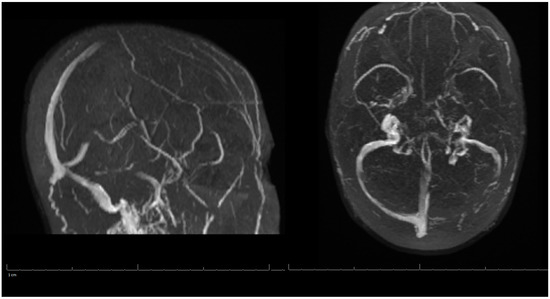

Additional labs showed Complete Blood Count (CBC) within acceptable limits, Basic Metabolic Panel (BMP) significant with glucose of 142 mg/dL, normal cardiac troponin level, and a negative urine drug screen. Urinalysis showed a small amount of blood but no evidence of infection. Genetic hypercoagulable labs, including antinuclear antibody, antineutrophil cytoplasmic antibodies, anti-cardiolipin, anti-Beta-2-glycoprotein, Factor V Leiden, and a lupus anticoagulant assay, were also unremarkable. Several hypercoagulable tests including antithrombin, protein C, and protein S were deferred, as results would have been confounded by the acute thrombotic event. Of note, the patient had abnormal findings on the lipid panel consisting of high cholesterol, triglyceride, and VLDL, and a low HDL level. Ultrasound Venous Doppler of the bilateral lower extremities showed no deep vein thrombosis. MRI brain/MRV (Magnetic Resonance Imaging (MRI) is a technique that uses magnetic fields and computer-generated radio waves to create images of organs and tissues in your body. Magnetic Resonance Venography (MRV) uses magnetic resonance technology and intravenous contrast dye to visualize the veins. Diffusion-Weighted Imaging (DWI) is a form of MRI that uses the diffusion of water molecules to generate images) with and without contrast confirmed acute venous infarct in the left subcortical frontal and parietal lobes as well as the left splenium of the corpus callosum. Thrombosis of the superior sagittal sinus, cortical veins, straight sinus, left internal cerebral vein, vein of Galen and the bilateral transverse sinuses, as well as the left sigmoid sinus, were also confirmed. A small hemorrhagic focus in the left occipital lobe was noted and was likely venous hemorrhages (Figure 1 and Figure 2). The final diagnosis was diffuse cerebral venous sinus thrombosis likely related to OCP use with possible contribution by recent COVID vaccination.

Figure 1. MRI of the Brain without contrast (DWI) (Magnetic Resonance Imaging (MRI) is a technique that uses magnetic fields and computer generated radio waves to create images of organs and tissues in your body. Magnetic Resonance Venography (MRV) uses magnetic resonance technology and intravenous contrast dye to visualize the veins. Diffusion-Weighted Imaging (DWI) is a form of MRI that uses the diffusion of water molecules to generate images).

Figure 2. MRV of the Head during Hospital Admission.